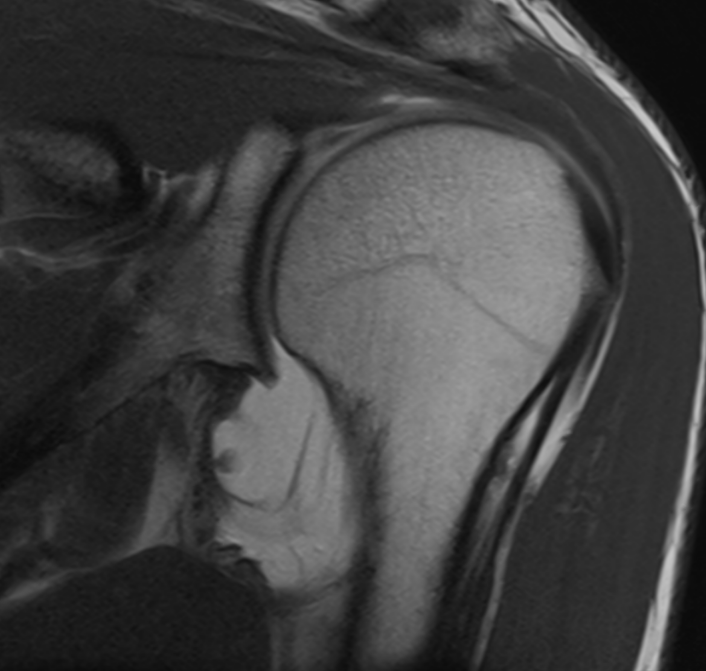

3. Inferior glenohumeral ligament injury post dislocation